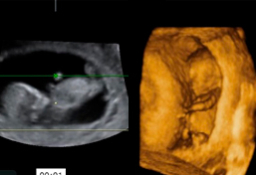

Feto de 12 semanas en ecografía de 2D y 3D

Así se ve un feto de 12 semanas de embarazo en una ecografía en 2D y en un ultrasonidos en 3D. En ambas se distingue los brazos y las piernas. Ecografía en 2D y 3D de feto de 12 semanas Podemos ver el bebé de 12 semanas de gestación en una imagen de dos dimensiones (a la izquierda, tumbado...